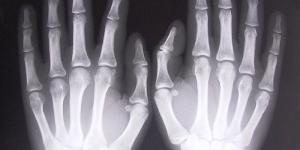

La artritis reumatoide es una enfermedad sistémica, predominantemente articular, que afecta sobre todo las pequeñas articulaciones de las manos y los pies, de forma simétrica. El curso es variable. Existen 7 criterios diagnósticos propuestos por el Colegio Americano de Reumatología, requiriéndose al menos...